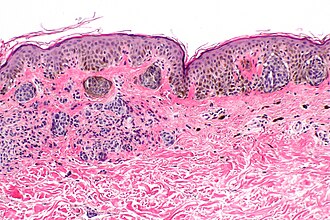

Template:Px Compound nevus. H&E stain. | |

| LM | nests of melanocytes in dermis and epidermis, melanocytes "mature" with depth, usu. no mitoses (occ. superficial), no destruction of surrounding structures, no conspicuous nucleoli, no significant melanocyte enlargement |

- Symmetrical lesion.

- "Matures" with depth.

- Less cellular with depth.

- Less nuclear atypia with depth.

- Smaller cells with depth.

- Smaller nests with depth.

- Rare mitoses (superficial).

- No deep mitoses.

- No destruction of surrounding structures.

- No nucleoli.

- In the dermis and epidermis - key feature.

The sections show melanocytes in the dermis and epidermis. The lesion is symmetrical in its architecture and pigment distribution. There is no pagetoid spread of melanocytes in the epidermis. Superficially, melanocytes are in nests. Melanocytes show no apparent cytologic atypia and mature with depth. No mitotic activity is appreciated. The lesion is completely excised in the plane of section.